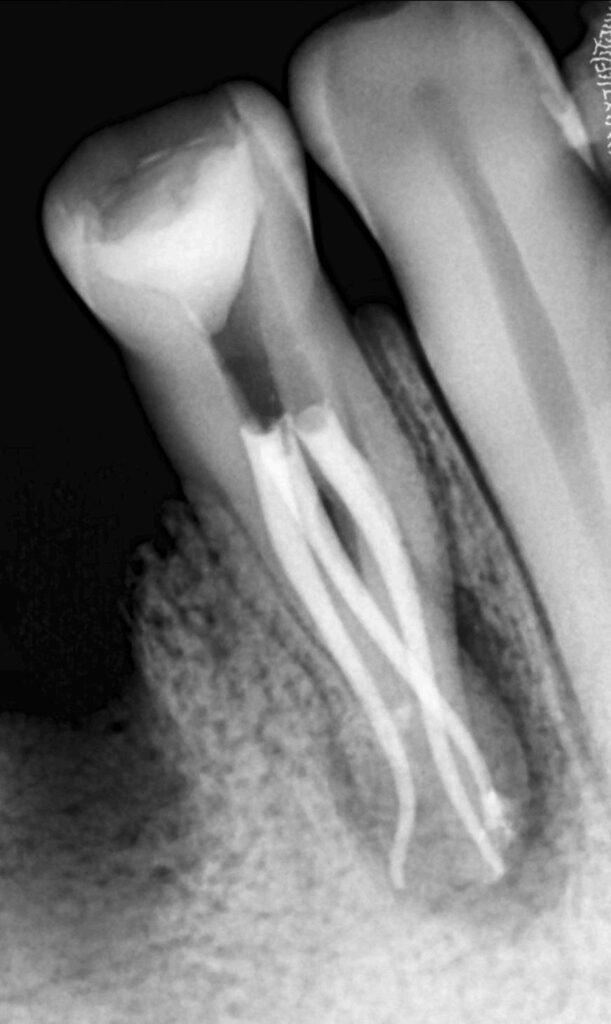

Obturación y resultado final

Se utilizó la técnica de condensación lateral con compactación hidráulica, empleando conos

de conicidad de 6% y cemento a base de resina.